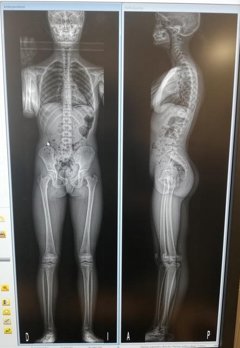

El Instituto Clavel y el Hospital San Francisco de Asís organizan la I Semana de la Columna Vertebral